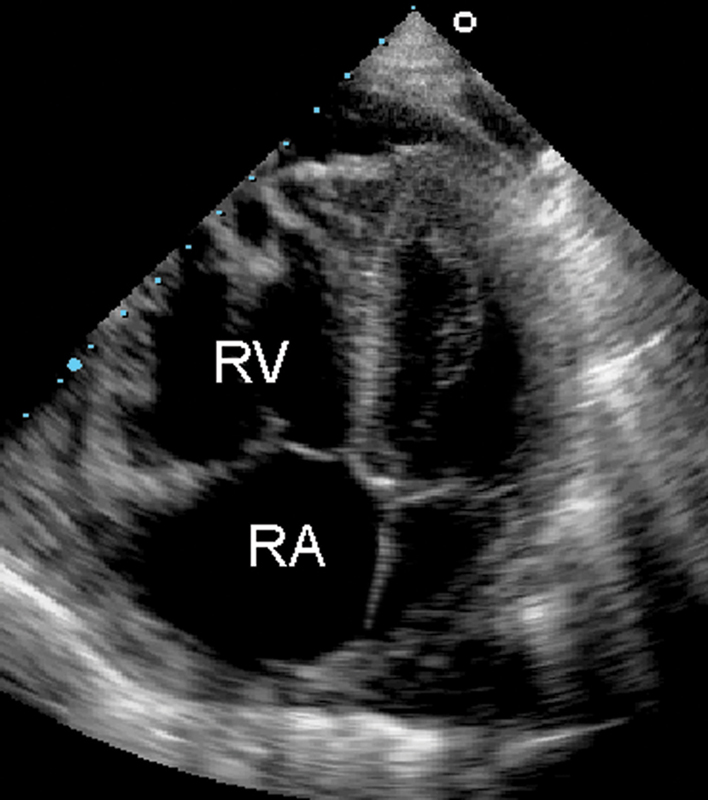

فحوصات تشخيصية لبعض امراض القلب والشرايين التاجية